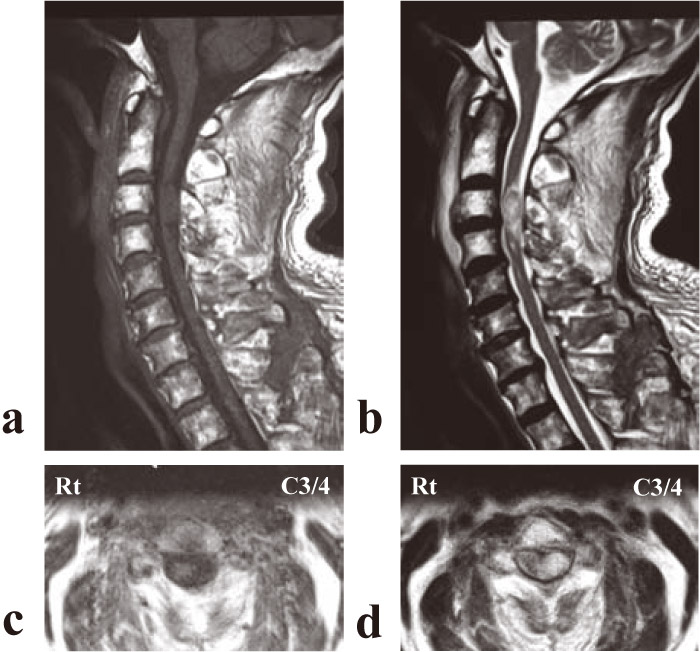

Fig.2

(a) T1-weighted midsagittal and (b) T2-weighted midsagittal of magnetic resonance imaging at the time of admission demonstrated a space-occupying lesion in the vertebral canal at the C3/4 level that showed an isointensity with the spinal cord on T1-weighted images and a high intensity on T2-weighted images. (c) T1-weighted axial and (d) T2-weighted axial views showed a round mass located on the left side of the spinal cord.

A 72-year-old man with a history of fall from stairs was admitted with incomplete left hemiplegia. He had a past medical history of intracerebral hemorrhage. He had no history of anticoagulant therapy. Routine blood tests, including coagulative parameters, were normal. Neurological testing demonstrated motor weakness of left upper limbs, showing grade 3/5 muscle strength, and left lower extremities showing grade 4/5 muscle strength. He had no sensory loss in his trunk or bilateral upper and lower extremities. Deep tendon reflexes were normal in both upper and lower extremities. Babinski signs were positive bilaterally. Radiologic examination detected swelling of the retropharyngeal space, along with a fracture line (called‘ fracture of the beak’) running from the anterior of the C3 vertebral body to the C3/4 intervertebral disk, plus a C4 spinous process fracture (Fig.1). A sagittal computed tomography (CT) image revealed the same type of fracture at C6 as seen at C3, along with spinous process fractures at C4, C7, Th1, and Th2 (Fig.1). We thus classified these fractures as stage 3 compressive flexion fractures under the Allen classification system. Midsagittal and axial MRI views showed a space-occupying lesion in the vertebral canal located on the middle to left side at the C3/4 level that showed isointensity with the spinal cord on T1-weighted images and high intensity on T2-weighted images (Fig.2). The mass had an oval shape and appeared to be located in the subdural or subarachnoid space. At a glance the mass looked ‘classic’ for an intradural tumor, we made an initial clinical diagnosis of either traumatic spinal subdural hematoma (SDH) or subarachnoid hematoma (SAH) because of the present history and the location of the mass. Because our patient had relatively minimal neurological symptoms, we initially chose a conservative approach in which we treated him by a halo-vest and Philadelphia color with the expectation that the mass would spontaneously regress over time. However, MRI one week after the injury and one month after the injury still showed no reduction in size and no signal change. MRI one month after the injury showed enhancement of the mass after intravenous administration of gadopentetate dimeglumine (Gd-DTPA) (Fig.3). A CT myelogram at this time revealed the presence of an intradural extramedullary tumor.